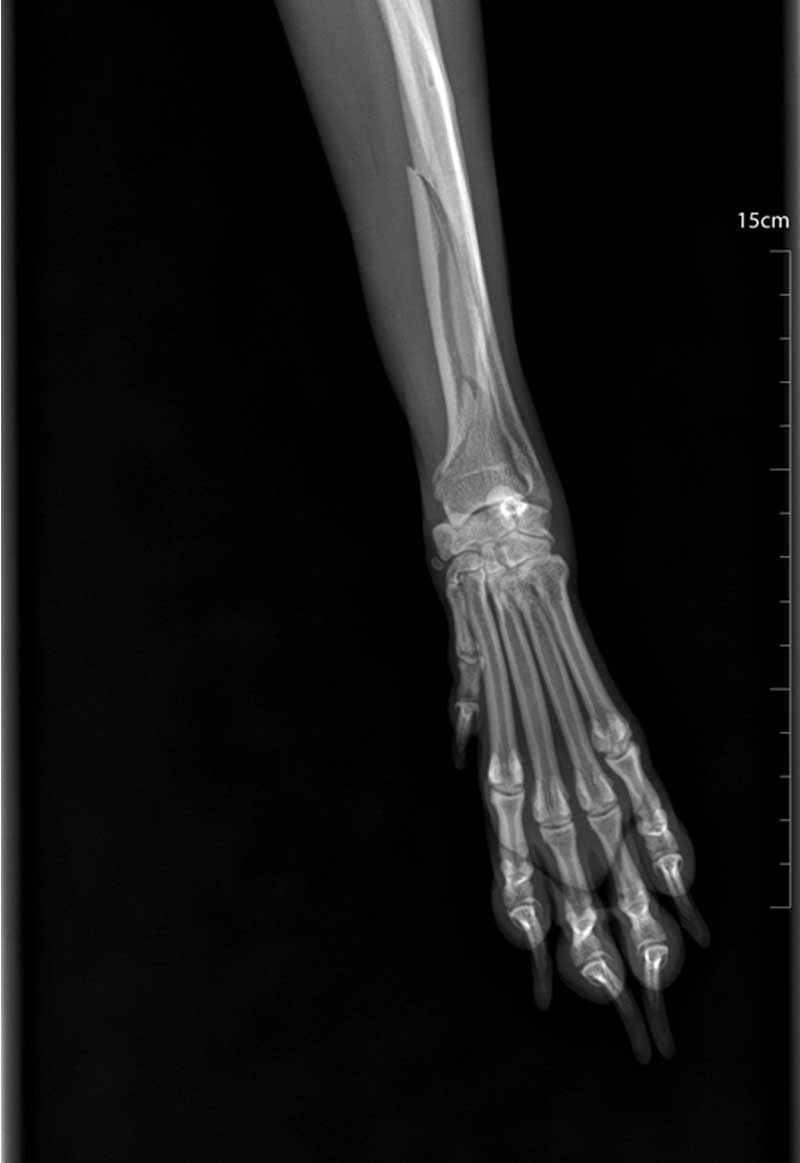

Dijagnoza se postavlja rendgenskim snimkama koje pokazuju lokaciju i tip prijeloma.

Liječenje može biti konzervativno, pomoću gipsa ili udlage, ili kirurško, uključujući pločice, vijke, čavle ili vanjsku fiksaciju.